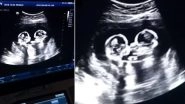

Foetal Rivalry? Twins Seen Fighting Inside Mom’s Womb During Ultrasound Scan in China (Watch Viral Video)